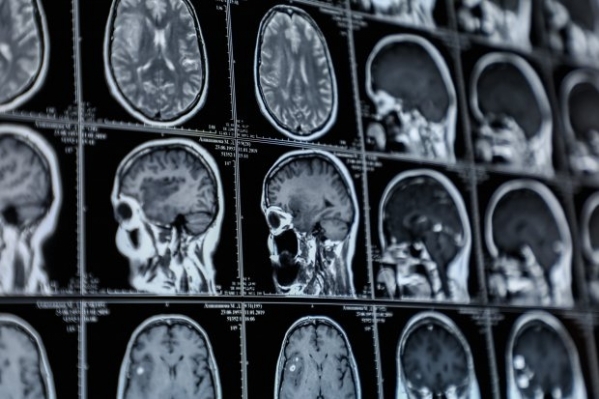

Как сообщает «Волгоградская правда.ру», сегодня в больницу №15 доставили современный аппарат для МРТ экспертного класса. Такой высококачественный прибор значительно уменьшит время процедуры магнитно-резонансной томографии.

Отметим, МРТ головного мозга на обычном аппарате занимает полчаса. На современном оборудовании исследование будет выполняться в течение нескольких минут. Все это позволяет сократить лучевую нагрузку на организм, поэтому МРТ можно будет проводить даже детям.

Новому МРТ-аппарату под силу «разглядеть» опухоль на самой ранней стадии.